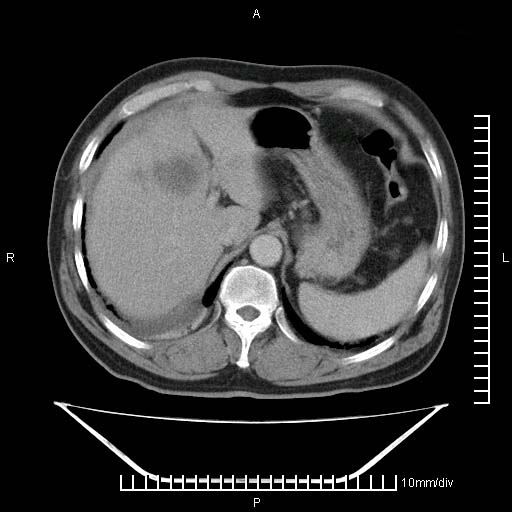

标题: CT25082:肝脏增强:男性,70岁 [打印本页]

标题: CT25082:肝脏增强:男性,70岁

患者以心脏疾病收住院,腹部无明显症状,b超查肝脏有占位。

增强效果不理想。考虑转移,胆囊壁明显增厚,不排除胆囊癌肝转移。

病灶无强化,考虑囊肿。

牛眼征,中心坏死无强化,外缘强化,最外缘又见低密度,考虑转移,与脓肿鉴别

肝内多发转移瘤,右下肺炎症并少量胸水。胃壁增厚建议胃镜,胰尾部“病变”为肠管。

1)肝脏多发性转移瘤(不排除胰尾癌转移所致可能)。2)腹水。3)右侧少量胸腔积液。

ct25082 结果:转移瘤

外院mr结果:胰尾恶性占位。